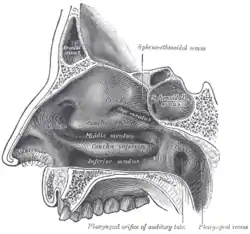

The nasal septum is composed of the quadrangular cartilage, the vomer bone (the perpendicular plate of the ethmoid bone), aspects of the premaxilla, and the palatine bones. Each lateral nasal wall contains three pairs of turbinates (nasal conchae), which are small, thin, shell-form bones: (i) the superior concha, (ii) the middle concha, and (iii) the inferior concha, which are the bony framework of the turbinates. Lateral to the turbinates is the medial wall of the maxillary sinus. Inferior to the nasal conchae (turbinates) is the meatus space, with names that correspond to the turbinates, e.g. superior turbinate, superior meatus, et alii. The internal roof of the nose is composed by the horizontal, perforated cribriform plate (of the ethmoid bone) through which pass sensory filaments of the olfactory nerve (cranial nerve I); finally, below and behind (posteroinferior) the cribriform plate, sloping down at an angle, is the bony face of the sphenoid sinus.

Internal nasal anatomy

In the midline of the nose, the septum is a composite (osseo-cartilaginous) structure that divides the nose into two similar halves. The lateral nasal wall and the paranasal sinuses, the superior concha, the middle concha, and the inferior concha, form the corresponding passages, the superior meatus, the middle meatus, and the inferior meatus, on the lateral nasal wall. The superior meatus is the drainage area for the posterior ethmoid bone cells and the sphenoid sinus; the middle meatus provides drainage for the anterior ethmoid sinuses and for the maxillary and frontal sinuses; and the inferior meatus provides drainage for the nasolacrimal duct.

The internal nasal valve comprises the area bounded by the upper lateral-cartilage, the septum, the nasal floor, and the anterior head of the inferior turbinate. In the narrow (leptorrhine) nose, this is the narrowest portion of the nasal airway. Generally, this area requires an angle greater than 15 degrees for unobstructed breathing; for the correction of such narrowness, the width of the nasal valve can be increased with spreader grafts and flaring sutures.